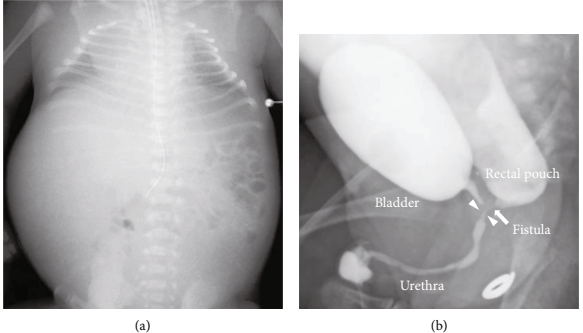

新生儿出生体重2473 g,1分钟Apgar得分为5分, 5分钟Apgar得分为7分,脐动脉血pH值 7.30、pCO2 45.8、PO2 24.1、BE-3.9。新生儿体格检查证实肛门闭锁,腹部明显肿胀。由于严重呼吸衰竭伴持续性肺动脉高压,新生儿需要立即插管和高频振荡通气并吸入一氧化氮治疗(图3a)。对于肛门闭锁,在第一天进行膀胱造口术,腹部超声显示尿道内有结石样高回声物。出生后36天,膀胱尿道造影显示高位肛门闭锁伴直肠尿道瘘未闭,下尿路无梗阻,直肠尿道瘘远端尿道狭窄(图3b)。出生后核磁共振没有显示任何脑异常,包括脑室周围白质软化及脑室内出血。新生儿经后矢状位肛门成形术后出院,无呼吸系统并发症,出生后19个月恢复良好。

图3. 新生儿胸部X线和膀胱尿道造影